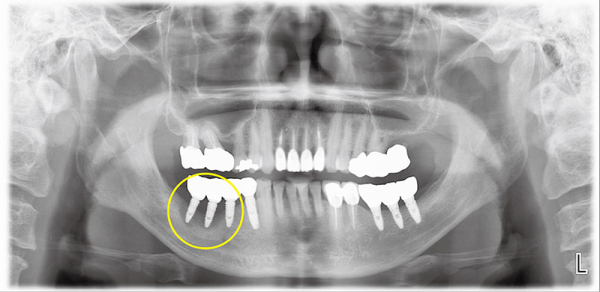

자료사진(그림1)은 식립한지 3년정도 된 임플란트 주변에서 냄새와 쓴맛이 난다고 치과에 내원한 환자다.

왼쪽아래 임플란트 나사들 주변으로 검은색 음영이 관찰되는데, 이는 임플란트 주변의뼈가 녹아있음을 의미한다. 잇몸뼈를 충분히 확보하지 않은 채 임플란트를 식립하여 불과 3년 만에 임플란트 표면이 노출되면서 주위염이 급속히 진행되고 주변의 뼈가 녹은 것으로 추정된다.

바로 옆 안쪽에서 네 번째 임플란트의 주변으로는 뼈가 비교적 온전하게 유지되고 있으나, 이것 또한 상부에 미약한 염증이 관찰된다. 결국 맨 뒤 임플란트 세 개를 제거하고 3개월이 지나 잇몸이 다 낫고 나서 충분한 높이와 두께로 다량의 골이식을 시행하였다.